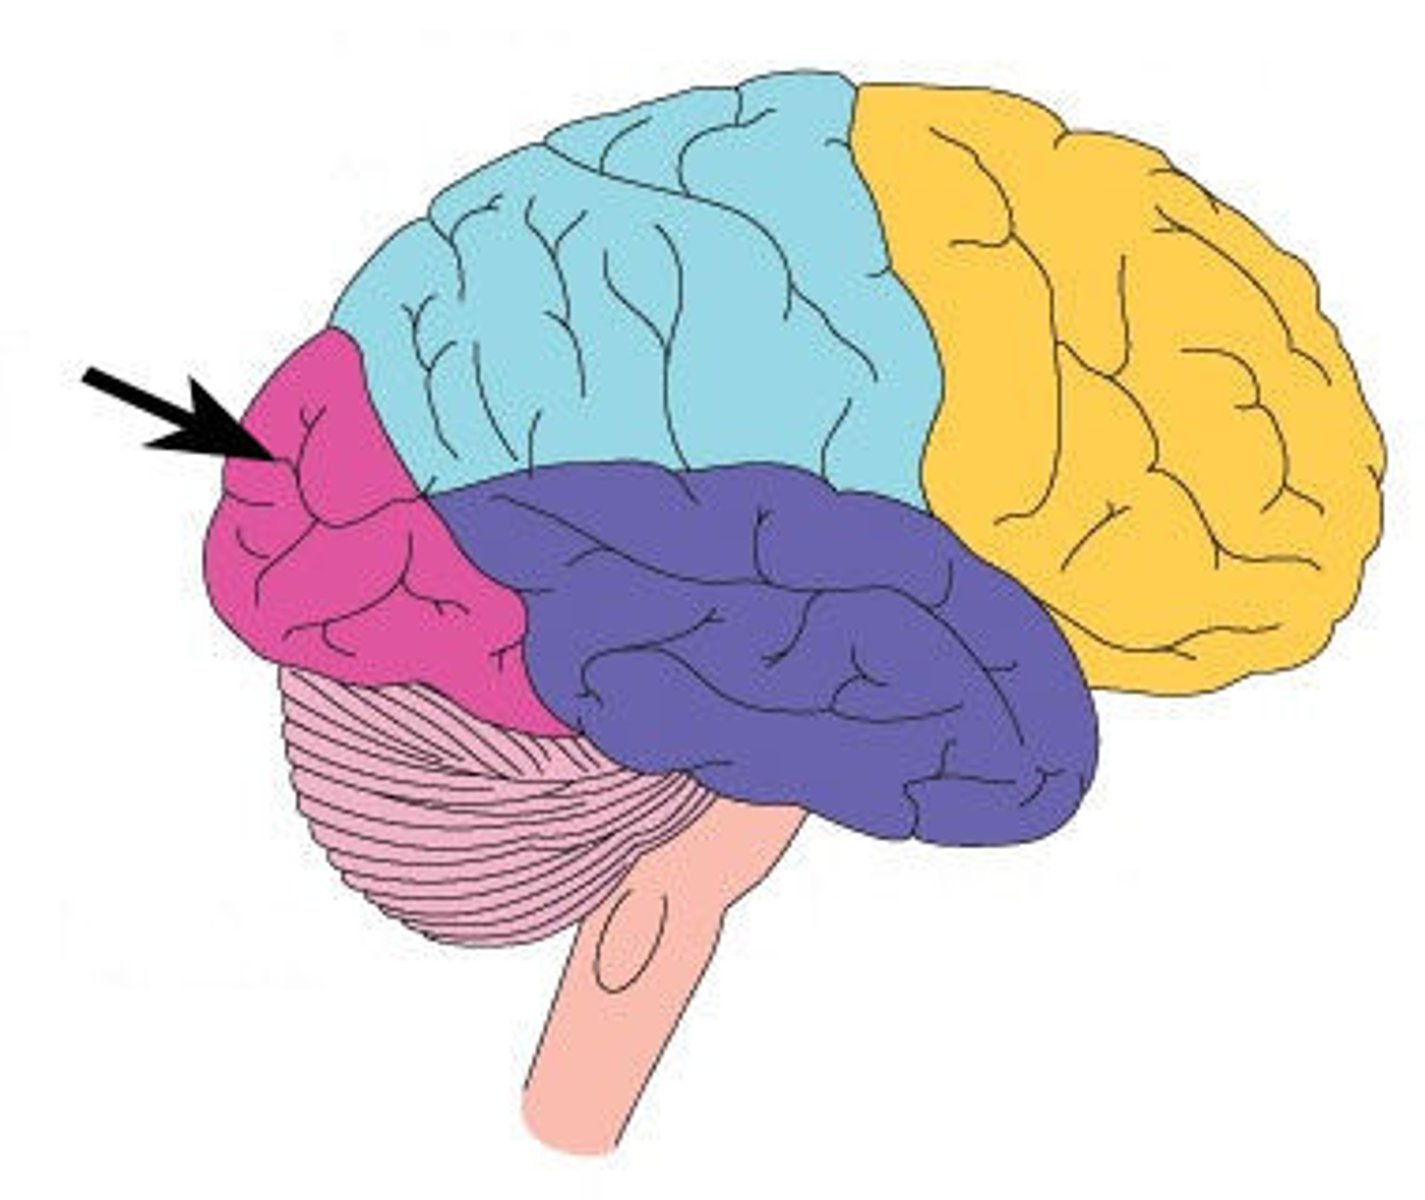

central sulcus

between postcentral and precentral gyri

longitudinal fissure

separates cerebral hemispheres

frontal lobe

associated with social cues, personality, planning, movement, emotions, and problem solving - contains primary motor cortex

precentral gyrus

primary motor cortex

parietal lobe

A region of the cerebral cortex whose functions include processing information about touch, contains primary somatosensory cortex

postcentral gyrus

primary somatosensory cortex

occipital lobe

visual center

temporal lobe

language centers, auditory processing, olfactory